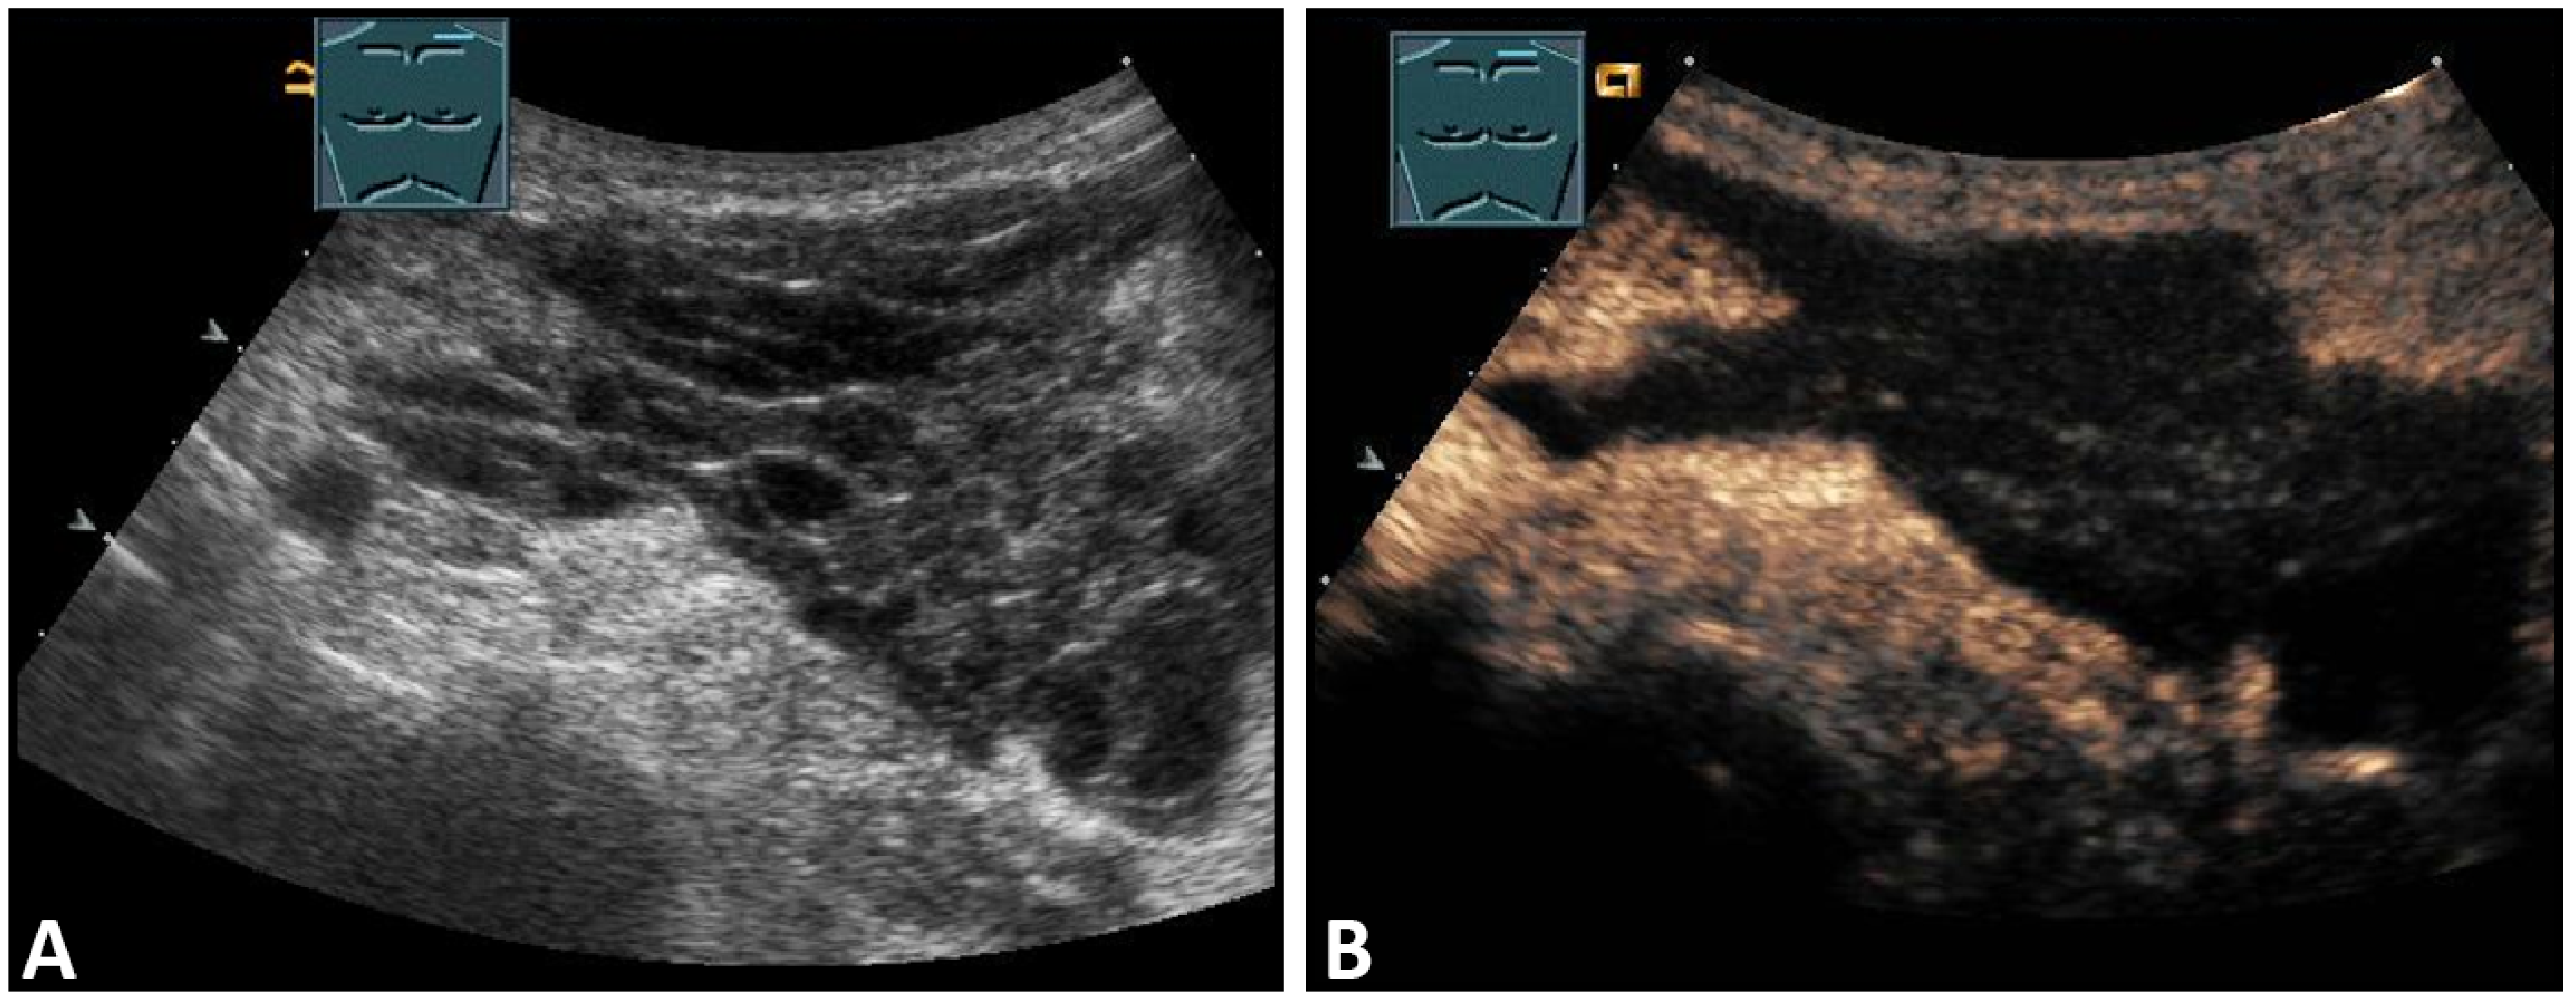

The suspicion of a chest wall abscess usually arises from the clinical presentation of the patient (swelling, redness, pain), and the role of ultrasound is to determine the extent of the process and its relation to adjacent structures. Depending on their stage, abscesses can have a very variable sonomorphology. The spectrum here ranges from mostly anechoic fluid collections with or without internal echoes to markedly inhomogeneous, anechoic structures that exhibit floating internal echoes under mild compression. An important feature of abscesses is their encapsulation, the detection of which allows the differentiation of abscesses and hematomas. On CEUS, the abscess capsule shows a marked enhancement (Figure 3).

Figure 3.

A patient with suspected granulomatous lung disease and a thoracotomy performed for histologic confirmation 7 days prior to US examination. Detection of a complex mass with gas containment on B-mode US (A). On CEUS, only enhancement of the capsule is observed (B), consistent with a cytologically confirmed abscess of the chest wall. The arrows mark the abscess capsule.